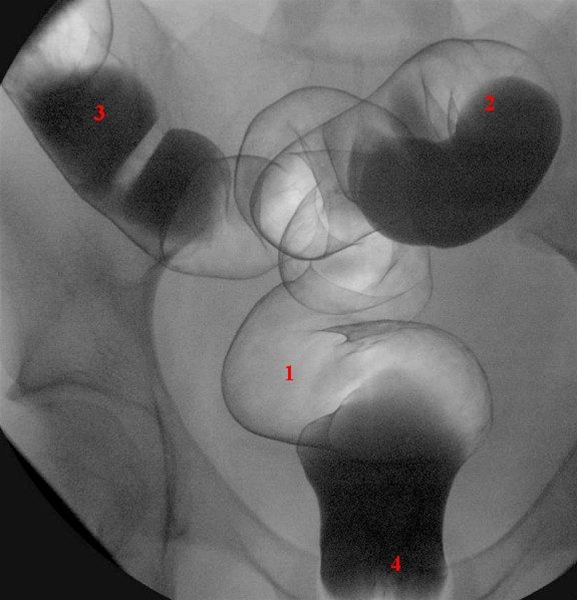

Rektum (1) og sigmoideum (2 og 3) i frontaloptagelse

Ballonkateter i rektum (4) er delvis skjult af barium-kontrast